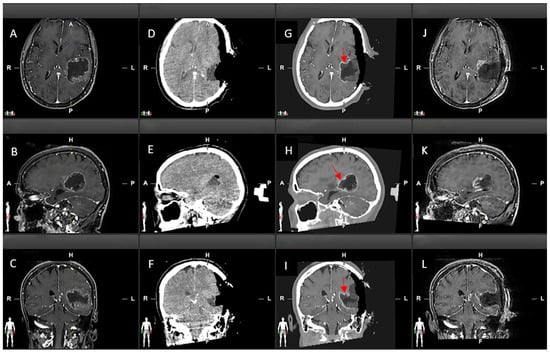

2.5. Qualitative Comparison of iCT, Virtual iMRI, and Post-Operative MRI

3.3. Qualitative Evaluation